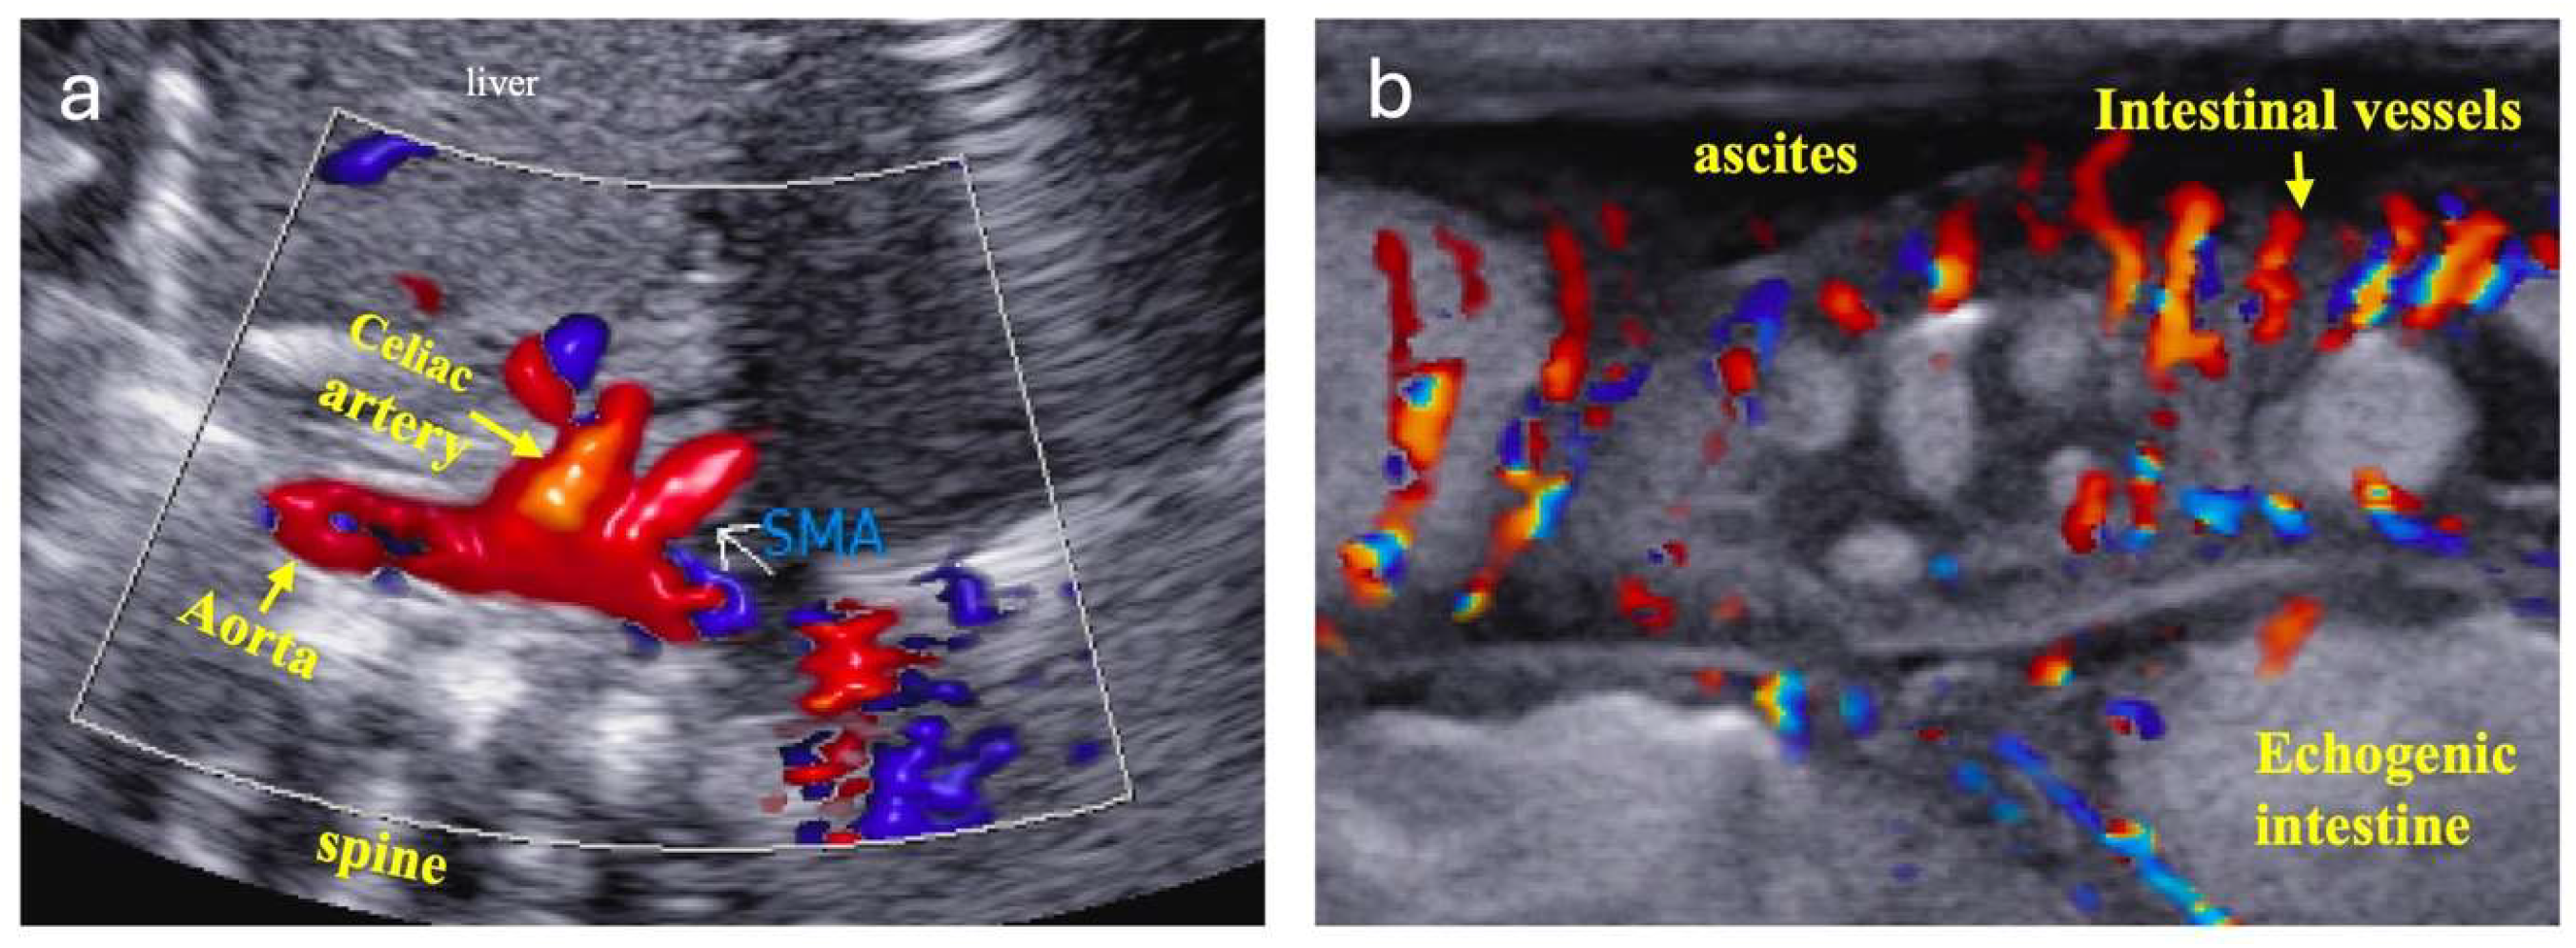

3.1. Monitoring Systemic Hypoperfusion and Hypoxia

3.2. Monitoring Pulmonary Overcirculation

- Chan, B.; Gordon, S.; Yang, M.; Weekes, J.; Dance, L. Abdominal ultrasound assists the diagnosis and management of necrotizing enterocolitis. Adv. Neonatal Care 2021, 21, 365–370. [Google Scholar] [CrossRef]